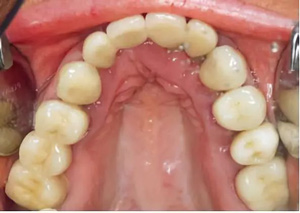

圖2-圖6:2013 年10 月15 日口內(nèi)狀況。

口外檢查未發(fā)現(xiàn)異常。牙齒和牙周狀態(tài)如圖1 和2-6所示??傮w來(lái)說(shuō),已有的修復(fù)體已不完善。第一次就診時(shí),檢查發(fā)現(xiàn)17、15、11、36、45 和46 號(hào)牙齒已缺失。16、14、12、27、37 和35 號(hào)牙齒已做過(guò)根管治療。所有剩余的牙齒牙髓活力測(cè)試均正常,叩診檢查未見(jiàn)異常。橋基牙37 已發(fā)生大面積的繼發(fā)齲,33 號(hào)牙齒齲壞和43 號(hào)牙齒繼發(fā)齲。16 和14 號(hào)牙齒根管充填不足且有根尖周炎。35 號(hào)牙齒的根管充填似乎是邊緣封閉、無(wú)氣泡,但也欠充。所有需要保留的牙齒的平均牙周附著喪失為5-6mm(最大9mm),探診深度(ST)為4-5mm(最大8mm)。27 號(hào)牙齒單獨(dú)的探診深度已達(dá)15mm。牙齦緣普遍松軟,下頜前牙舌側(cè)區(qū)域附著堅(jiān)硬的菌斑。整個(gè)邊緣牙齦發(fā)生炎癥性改變,特別是腭側(cè)區(qū)域。